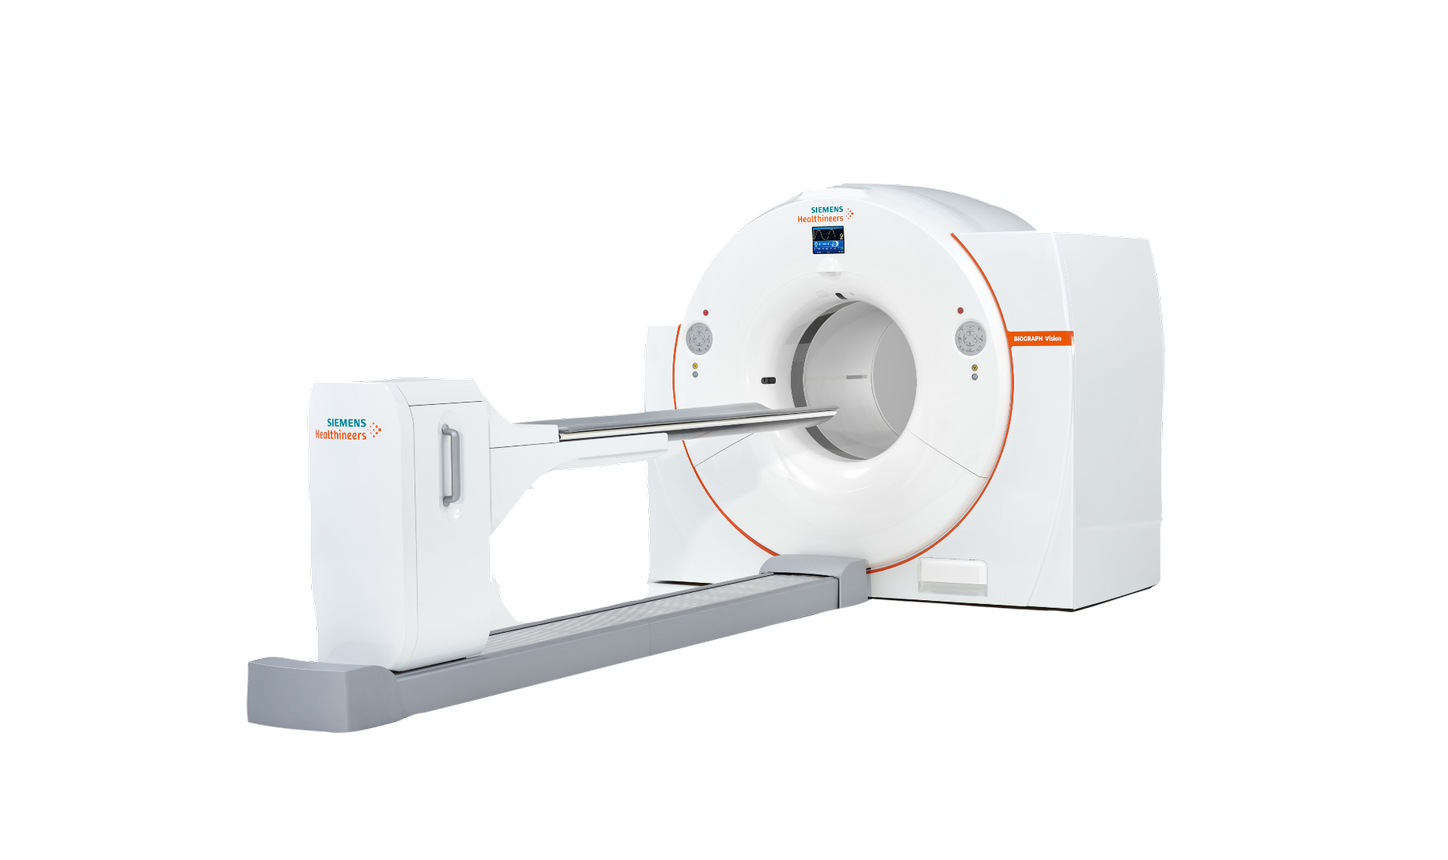

Answering to clinical needs in oncology, neurology, cardiology, and radiology, Siemens Healthineers Molecular Imaging systems provide PET/CT, SPECT, and hybrid SPECT scanner (SPECT/CT) solutions to help clinicians diagnose, treat, and monitor diseases more confidently.